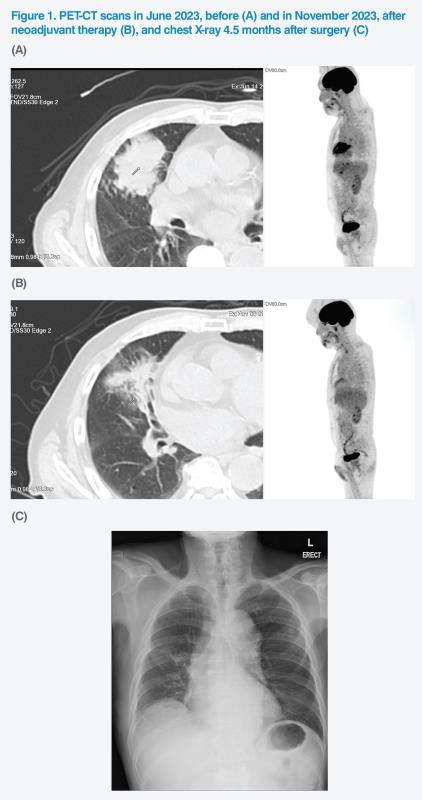

The hypermetabolic lung mass measured 7.3 x 6.8 cm and had a maximum standardized uptake value (SUVmax) of 15.9. (Figure 1A) The patient’s ipsilateral paratracheal, hilar and subcarinal lymph nodes (LNs) were hypermetabolic, suggesting stage III disease (stage IIIB, T4N2M0 disease based on the 8th edition of the AJCC staging criteria).1,2 CT-guided biopsy confirmed squamous-cell non-small-cell lung cancer (NSCLC). Molecular testing confirmed EGFR-negative disease with insufficient tissue for further ALK and PD-L1 expression level testing.

The patient completed neoadjuvant therapy on 11 October 2023. He tolerated treatment well, with no dose reductions or treatment interruptions. Follow-up PET-CT scan showed substantial gross reduction of the lung mass to 7.0 x 3.5 cm. SUVmax declined to 4.3. (Figure 1B)

Postoperative pathology report confirmed that the patient achieved pathological complete response (pCR). After discussing succeeding treatment options, the patient and his family decided to have no adjuvant therapy. The patient was last seen on 11 April 2024 and remained well. (Figure 1C) He will be regularly monitored for signs of disease progression.